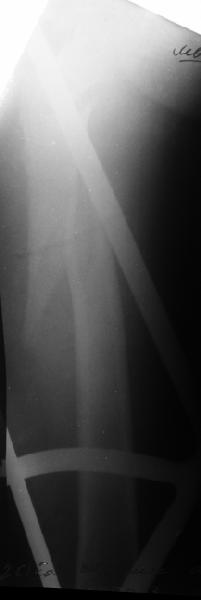

Да, сейчас это и у нас самый напрашивающийся выбор. Сделали гвоздем ChM, картинки в приложении.

У молодых реконструкционный гвоздь самое то. При остеопорозе надо что-то помассивнее.